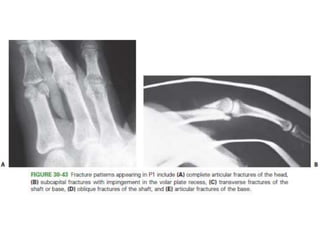

• #72 Fracture patterns appearing in P1 include (A) complete articular fractures of the head, (B) subcapital fractures with impingement in the volar plate recess

• #73 (C) transverse fractures of the shaft or base, (D) oblique fractures of the shaft, (E) articular fractures of the base.